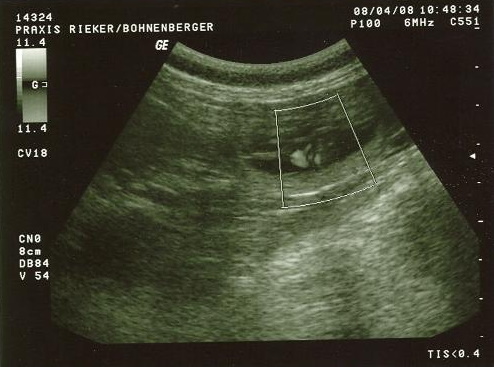

| 08.04.2008 |

Wir waren beim Ultraschall und haben eine werdende

Mami!

Hier ist der Beweis!!!

Unser Doc hat es extra nochmals eingegrenzt, zwecks

der besseren Erkennbarkeit